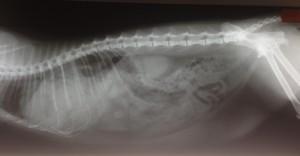

Najpogostejše poškodbe, ki spremljajo zlome pri mačkah, so raztrganine trebušne prepone, vezivno mišične opne, ki razmejujejo prsno in trebušno votlino, pretresi možganov, zlomi lobanjskih kosti, čeljusti, hrbtenice, poškodbe perifernih živcev, krvavitve v telesne votline ali poškodbe notranjih organov (podplutbe v področju ledvic, raztrganine sečnega mehurja ali sečnice, poškodbe pljuč, jeter, prebavil, trebušne slinavke …) (Slika 1).